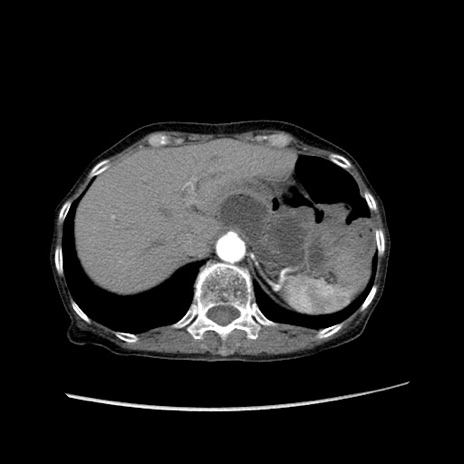

症例25(横断像)

【症例】80歳代女性

【主訴】胸のつかえ感

【現病歴】約9時間前に食後から胸のつかえた感じあり、嘔吐あり、来院。

【既往歴】胃癌(全摘)、胆摘、虫垂炎

【身体所見】心窩部に圧痛あり、反跳痛なし。

【データ】WBC 5700、CRP 0.05